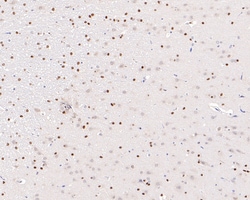

Invitrogen™ Phospho-ATF2 (Thr71) Recombinant Rabbit Monoclonal Antibody (SC05-90)

The transcription factor ATF-2 (also called CRE-BP1) binds to both AP-1 and CRE DNA response elements and is a member of the ATF/CREB family of leucine zipper proteins. ATF-2 interacts with a variety of viral oncoproteins and cellular tumor suppressors and is a target of the SAPK/JNK and p38 MAP kinase signaling pathways. Various forms of cellular stress, including genotoxic agents, inflammatory cytokines and UV irradiation, stimulate the transcriptional activity of ATF-2. Cellular stress activates ATF-2 by phosphorylation of Thr69 and Thr71. Both SAPK and p38 MAPK have been shown to phosphorylate ATF-2 at these sites in vitro and in cells transfected with ATF-2.

| Immunohistochemistry (Paraffin), Western Blot, Immunocytochemistry | |